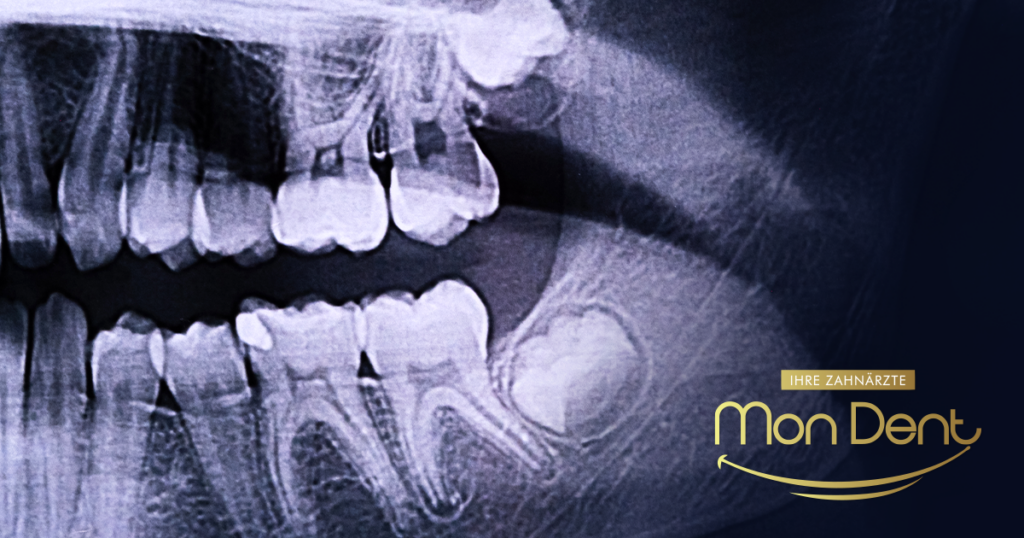

Kdaj je treba odstraniti modrostne zobe?

Umnjaci koji rastu krivo ili izazivaju bol trebaju vađenje. Saznajte kada umnjaci prave problem i kada je vađenje neophodno. Savjeti za siguran oporavak.

Umnjaci koji rastu krivo ili izazivaju bol trebaju vađenje. Saznajte kada umnjaci prave problem i kada je vađenje neophodno. Savjeti za siguran oporavak.